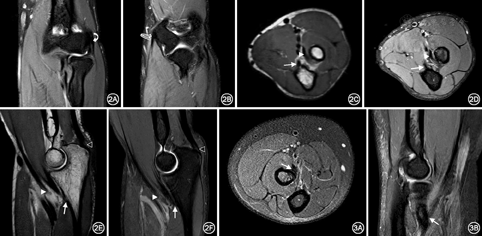

20例(40侧)正常志愿者的肘关节肌腱结构在MR各序列上均表现为细线样或条带状低信号,肌纤维走行连续(图2)。屈肌总腱、伸肌总腱在冠状位显示最佳;肱肌肌腱、肱二头肌腱在轴位和矢状位显示最佳,肱三头肌腱在矢状位和轴位显示最佳。伸肌总腱起于肱骨外上髁,MR表现为均匀细线样低信号(图2A)。屈肌总腱起源于肱骨内上髁,MR表现为均匀条状低信号(图2B),其深层线样低信号为内侧副韧带前束,起于肱骨内上髁前下部,止于尺骨冠突内侧。肱二头肌腱远端表现为条带状低信号,穿过肘窝附着于桡骨粗隆(图2C,图2D,图2E,图2F和图3),其远端无腱鞘,但有滑囊(桡侧囊)与桡骨粗隆紧密结合。肱肌肌腱远端,表现为条带状低信号,远端插入尺骨近端骨皮质(2C~2F)。肱三头肌腱远端结构分三层,长头和外侧头肌纤维在远端构成联合腱插入尺骨鹰嘴,表现为纤维结构连续的带状低信号(2E、2F),内侧头肌腱很短插入鹰嘴前方。

38例肘关节外伤患者,44条肌腱损伤,其中伸肌总腱损伤14例(6例伴桡侧副韧带损伤,2例伴肘关节骨折及桡侧副韧带损伤,1例伴肘关节脱位、尺侧副韧带及外侧副韧带复合体损伤,1例伴尺侧副韧带损伤),MR表现为伸肌总腱肱骨外上髁附着处部分纤维走形不连续性,PD-FS序列信号增高,局部被液体充填(图4)。屈肌总腱损伤10例(1例伴肘关节脱位、尺侧副韧带及外侧副韧带复合体损伤,3例伴尺侧副韧带损伤,1例伴肘关节脱位及环状韧带损伤),MR表现为纤维走形连续性不佳,T1WI序列呈低信号,PD-FS序列呈高信号,其周围软组织水肿(图5)。肱二头肌腱损伤3例(2例伴肘关节脱位、尺侧副韧带及外侧副韧带复合体损伤),MR表现为肱二头肌腱远端迂曲增粗,部分纤维不连续,桡骨粗隆附着点处T1WI序列呈低信号,PD-FS序列呈高信号改变,伴桡骨头脱位,骨髓及周围软组织水肿,关节腔积液(图6)。肱肌肌腱损伤7例(1例伴尺侧副韧带损伤,1例伴肘关节骨折,伴肘关节脱位及环状韧带损伤1例),MRI表现为肱肌腱尺骨粗隆附着端迂曲,T1WI序列呈水样低信号,PD-FS序列腱鞘走行区内信号增高,腱鞘积液(图7)。肱三头肌腱损伤10例(其中1例伴有骨折),MR表现为肱三头肌腱远端长头和外侧头部分撕裂,表现为迂曲增粗,鹰嘴附着端部分纤维不连续,T1WI序列纤维增粗,形态不规则,呈低信号改变,PD-FS序列肌纤维迂曲增粗,其内可见条状高信号改变,为纤维部分撕裂被液体充填所致(图8)。